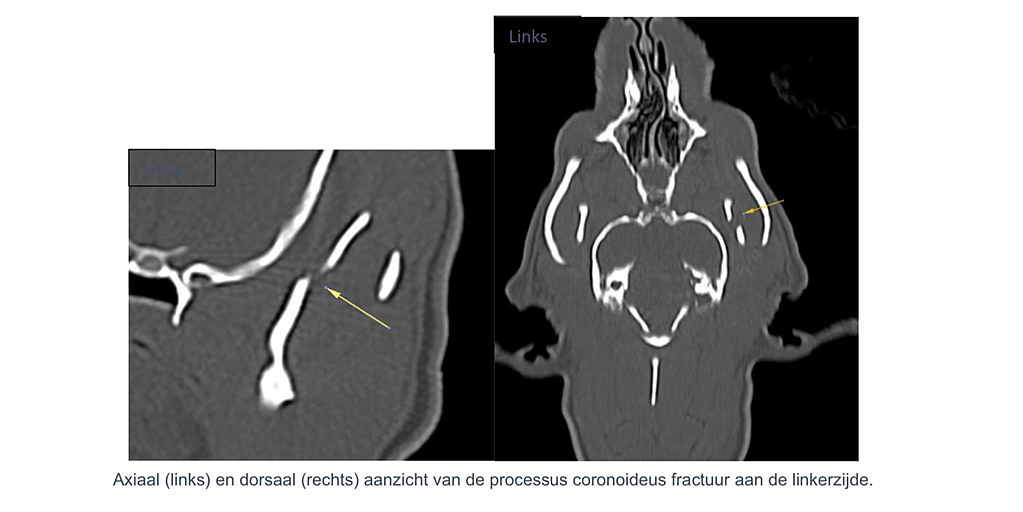

Verschuiving is goed zichtbaar op de 3D-reconstructie. - Linker processus coronoideus – complete overlangse fractuur

Sagittale reconstructies tonen een overlangse complete fractuurlijn, matig verplaatst, doorheen de volledige hoogte van de coronoid. - Processus condylaris bilateraal – intra-articulaire fracturen